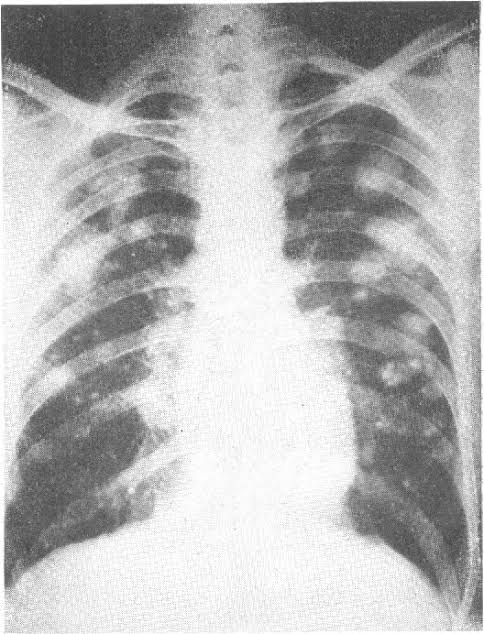

Causes of caplan syndrome

Caplan syndrome is also known as rheumatoid lung silicosis, silicoarthritis and rheumatoid pneumoconiosis. Inflammation leads to scarring of lung due to breathing of coal dust in persons with rheumatoid arthritis are the causes of Caplan syndrome.